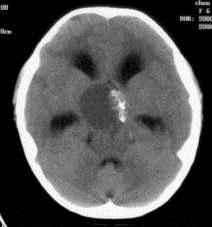

问题 病历摘要:??患者女性,6岁,半年来感觉视力模糊,近10天出现反复头痛,间有恶心呕吐,精神转差,查体:神志清楚,身高90cm,体重25Kg,血压90/55mmHg,右眼视力4.6,左眼视力4.8,双侧视乳头水肿,颈软,伸舌居中,四肢肌张力正常,肌力5级,双侧Babinski征(-)。 患者术后第一天,神志嗜睡,精神疲倦,皮肤干燥,38.2℃,心率155次/分,Bp102/60mmHg,中心静脉压3mmHO,Na160mmol/L,尿量很多,色清如水,应作的处理措施有?